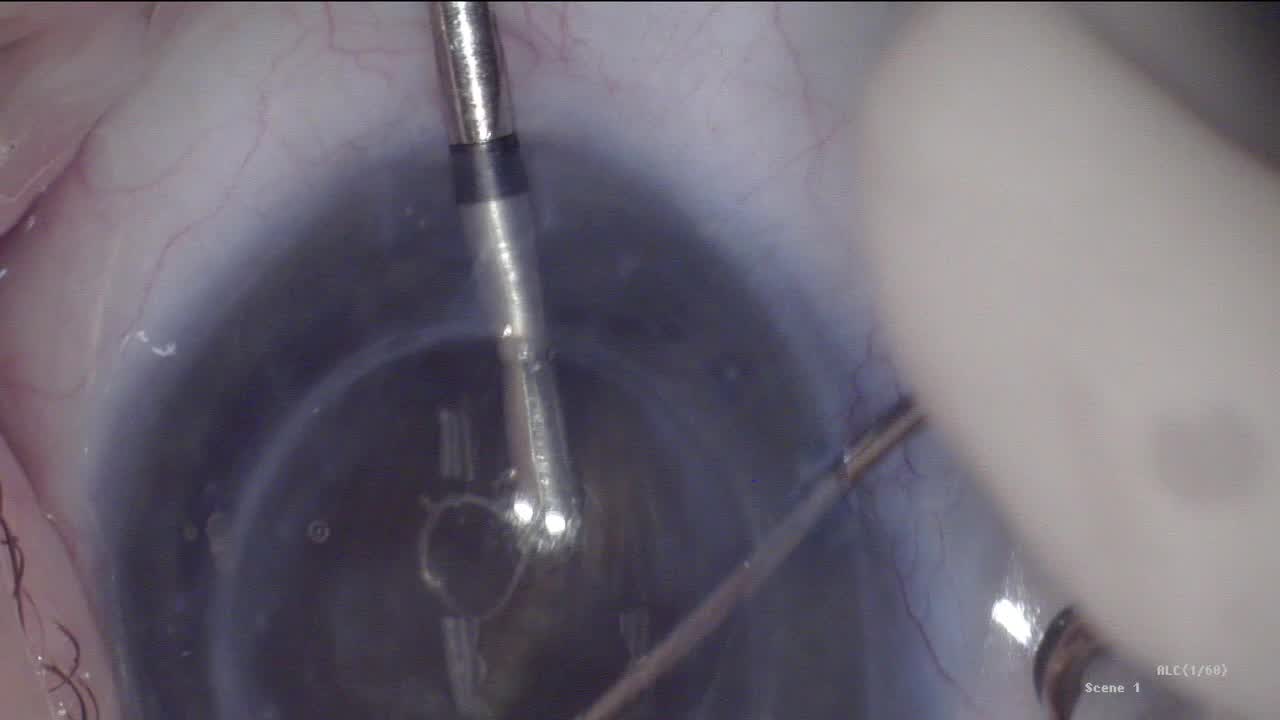

iDose TR® Live Procedure Broadcast

John Berdahl, MD; Iqbal Ike K. Ahmed, MD, FRCSC; Lorraine M. Provencher, MD; and Savak Teymoorian, MD, MBA

Live Demonstration: iDose TR® Implantation